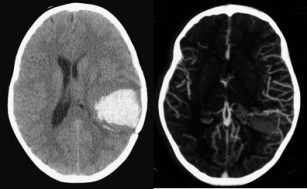

- se baser sur l’angioscanner pour localiser l’angiome par rapport à l’hématome. Cet examen permet de savoir dans quelle région de la cavité de l’hématome on trouvera le nidus.

dans l’exemple ci-dessous, on identifie les pédicules artériels décochés par les branches sylviennes « en passant ». la corticotomie en arrière du nidus permet d’identifier les pédicules artériels (« straight« ) en respectant les veines artérialisées tortueuses (« coils« ). après dissection circonférentielle des artérioles, celles ci sont coagulées et sectionnées, en circonscrivant progressivement le nidus et en terminant par le ou les pédicules veineux.